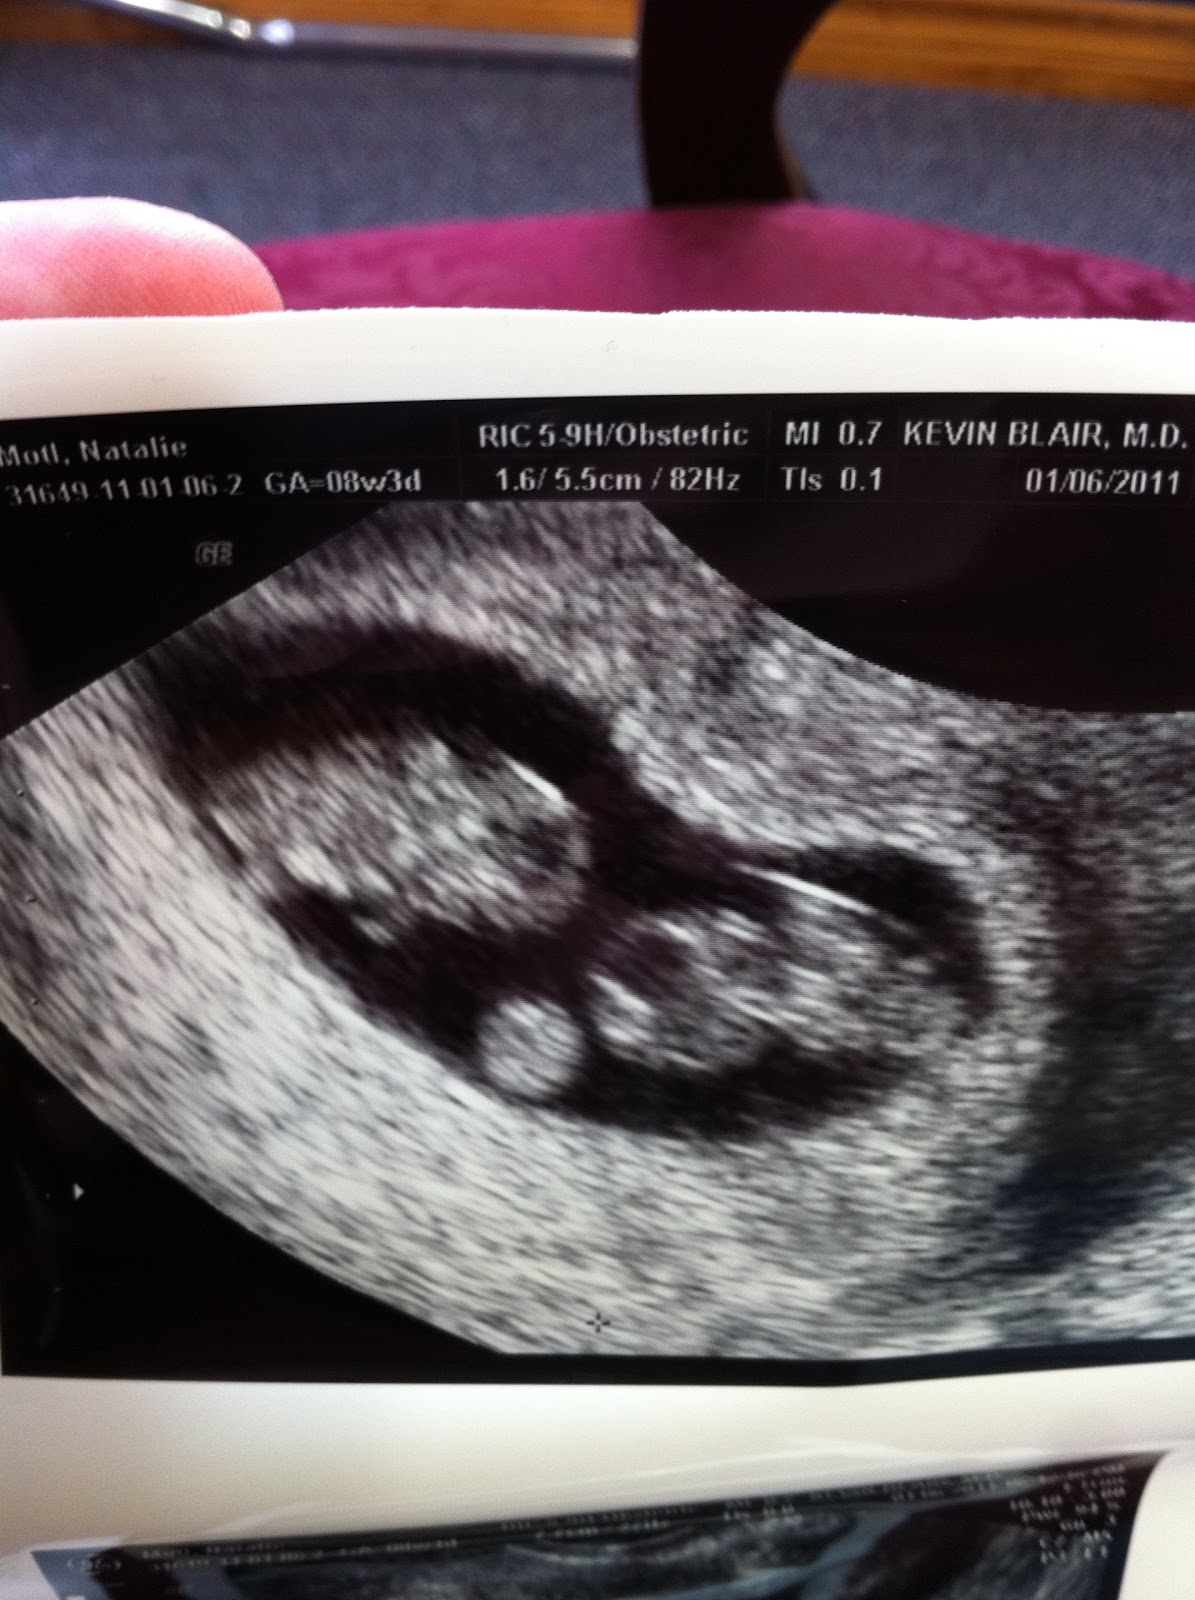

8 week ultrasound TWINS with heartbeats. IVF YouTube When Can An Ultrasound Detect Twins when will you find out you're having twins? technically, a twin can hide out in your uterus, but only for so long. Typically, you'll find out if you're having twins during a first trimester. A twin pregnancy raises the risk of complications for the pregnant. in most cases, twins can be detected as early as seven weeks. When Can An Ultrasound Detect Twins.